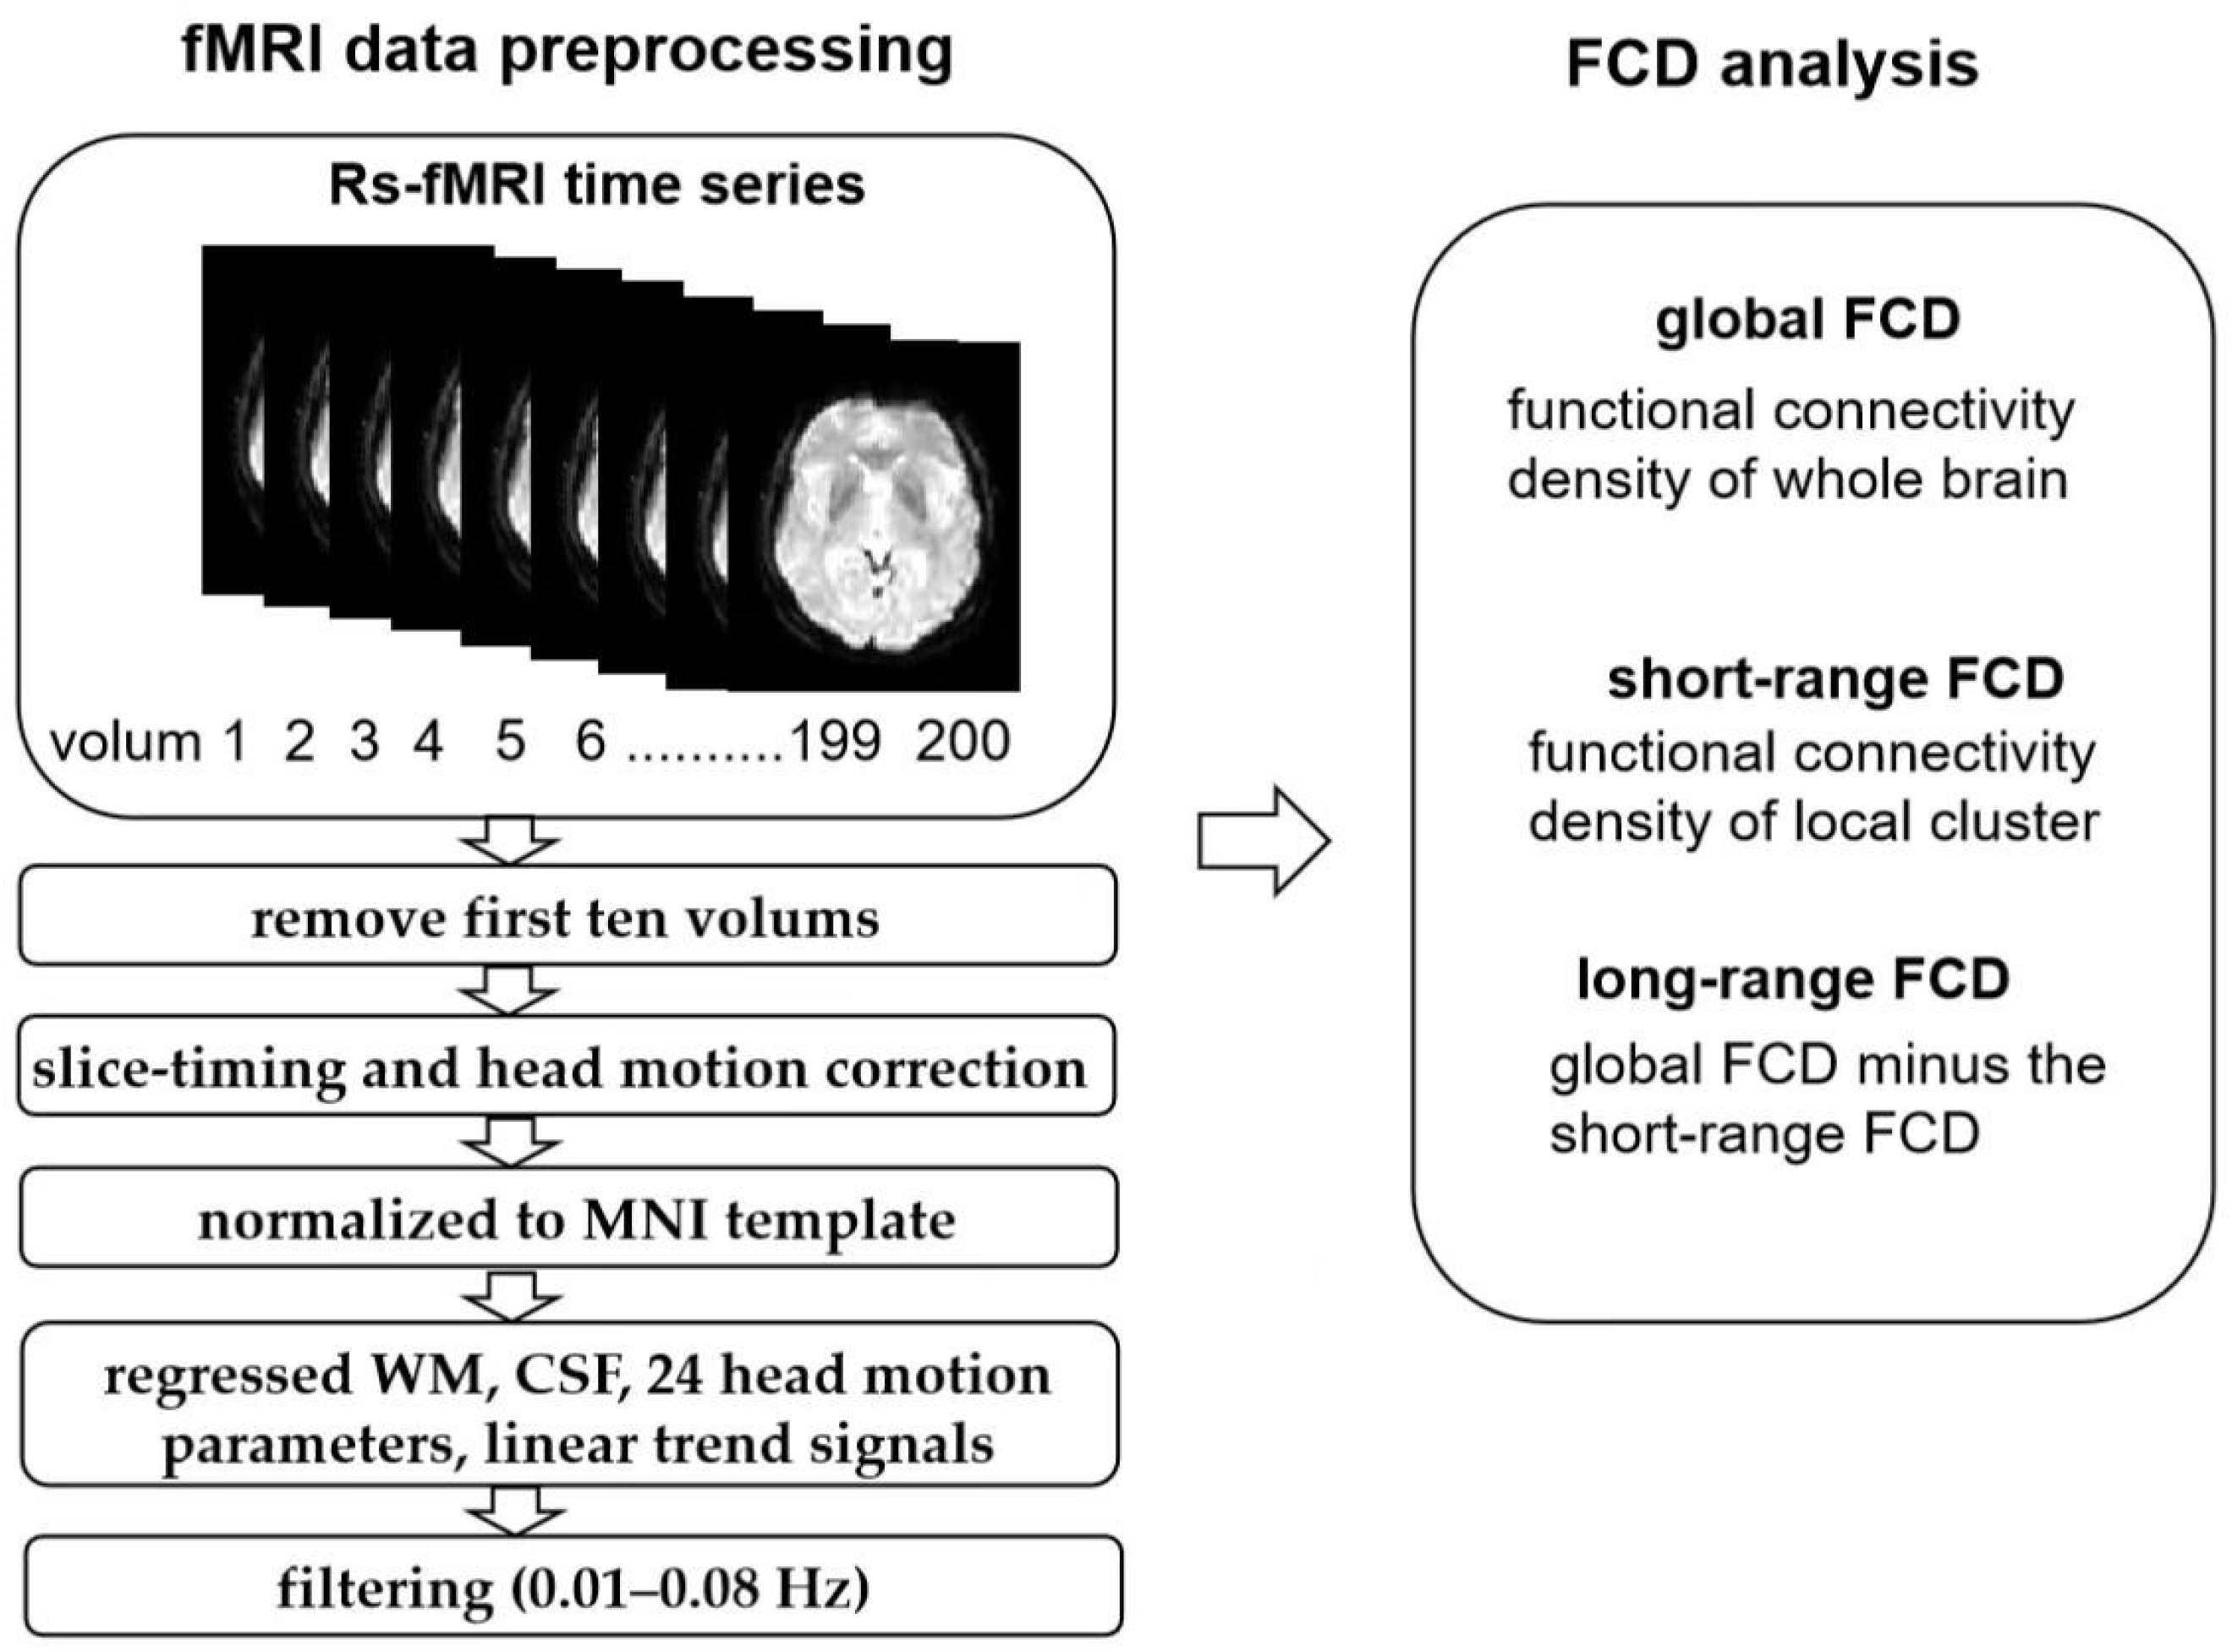

2.4. Resting-State fMRI Data Analysis